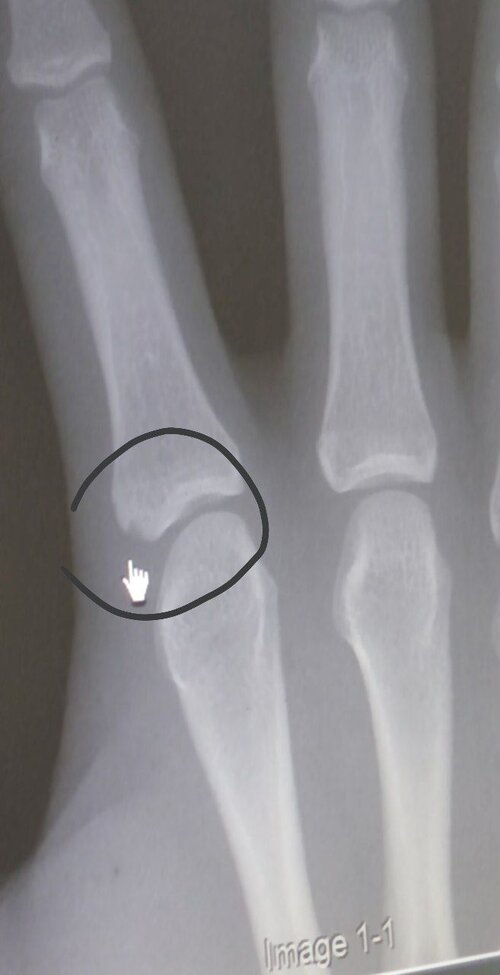

Do u have data on age of closure for those plates, thats more what im looking forUnfortunately I can't edit the post now, but its really unlikely that your femur & tibia plates are fused and your knees aren't, so I'd still use your knee xray over most things

I mean they aren’t exactly partially fused like the images you presented, they are a bit open. There’s a decent sized crack and not almost slim shut like those photos.by the way, if your knee plates are fused its very likely your wrists have aswell, spamming AI won't reopen ur plates

what letter would you assign them? do you have the pics on you? cause that would helpI mean they aren’t exactly partially fused like the images you presented, they are a bit open. There’s a decent sized crack and not almost slim shut like those photos.

don’t have the pics sadly the scan was in september but I’d rate it D-E.what letter would you assign them? do you have the pics on you? cause that would help

D-E is still extremely open and you've got plenty of growth left loldon’t have the pics sadly the scan was in september but I’d rate it D-E.

but yes, getting knee xrays to determine your growth plate closure is a better option than a wrist xray, but its just a lot simpler to actually go ahead and get an xray of your wrists

The claim "Hand plates are the earliest plates to close after ankle plates, meaning they can last for another 1-2 years." is also in a way true, but I wouldn't say they last for 1-2 years, closer to 6-9 months (in that time you can't grow more than 2cm realistically)